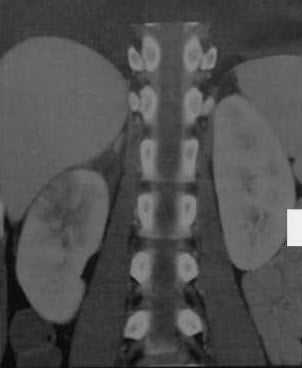

Острый очаговый пиелонефрит справа, фронтальная реконструкция кортикальной фазы КТ. Сегментарный участок пониженного контрастирования в верхнем полюсе. Снижение контрастирования верхней трети почки.

а, b Острый диффузный двусторонний пиелонефрит. Аксиальная (а) и фронтальная (b) КТ в кортикальной фазе. Множественные сегментарные участки сниженной перфузии в виде полос в корковом веществе почек.